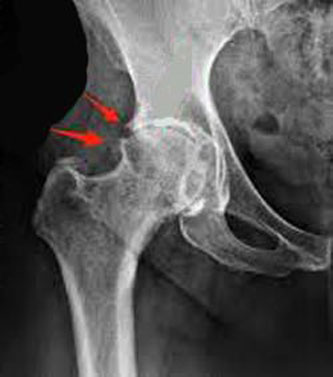

Os osteófitos são visíveis na radiografia em forma de uma protuberância óssea (um “chifrinho”). Habitualmente, os osteófitos em si não necessitam nenhum tratamento.

O que é importante é diagnosticar e tratar a artrose e suas consequências musculares, tendíneas e ligamentares em torno da articulação, para que a pessoa volte a ter um estilo de vida saudável. Abaixo, algumas imagens de livros e em raios-x, pra que agora todos possam identificar um osteófito quando for mencionado pelo profissional da área de saúde que lhe está atendendo.

Osteófitos em um quadril com artrose – visão pelos raios-x.